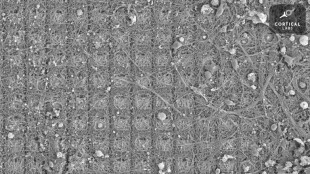

Neuronas de laboratorio aprendieron a jugar un videojuego (estudio)

Células cerebrales cultivadas en un laboratorio aprendieron a jugar el clásico videojuego Pong y podrían ser capaces de un "comportamiento inteligente y consciente", concluyeron neurocientíficos australianos.